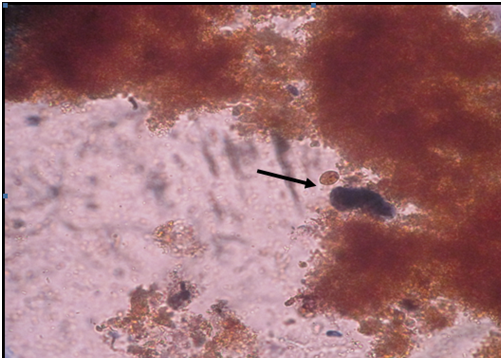

Full history, general examination, random blood sugar test (RBS), Hb and hemoglobin A1c levels were performed for each participant.16 Also demographic data and risk factors for parasitic infections were filled for all participants. Stools samples were obtained from children after the full explanation of the process to them. Fresh faecal samples were collected in dry labeled, plastic containers, with tight fitting covers and they were taken with caution not to be contaminated with urine.5 The samples were transported immediately to the Department of Parasitology zagazig university, where lab assessments were done. Stools samples were examined by direct wet17 and iodine stained smears18 and formol-ether concentration method for the routine screening of ova and parasites diagnostic stages (Figures 1‒10 ).19 Each sample was examined separately. Smears were prepared from sediments of formol-ether concentration for modified ziehl neelsen staining to detect intestinal coccidian and Cryptosporidium spp.19 Slides were examined by light microscopy at ×100, ×400 and ×1000 magnifications. Stools culture on nutrient agar was also done for detection of some intestinal parasites diagnostic stages.20 Patients with T1DM were divided according to the presence or absence of intestinal parasitic diagnostic stages in their stools into two main groups

Figure 7 Stools smear stained with modified Ziehl –Neelsen stain showing Cryptosporidium spp. oocyst (x1000).